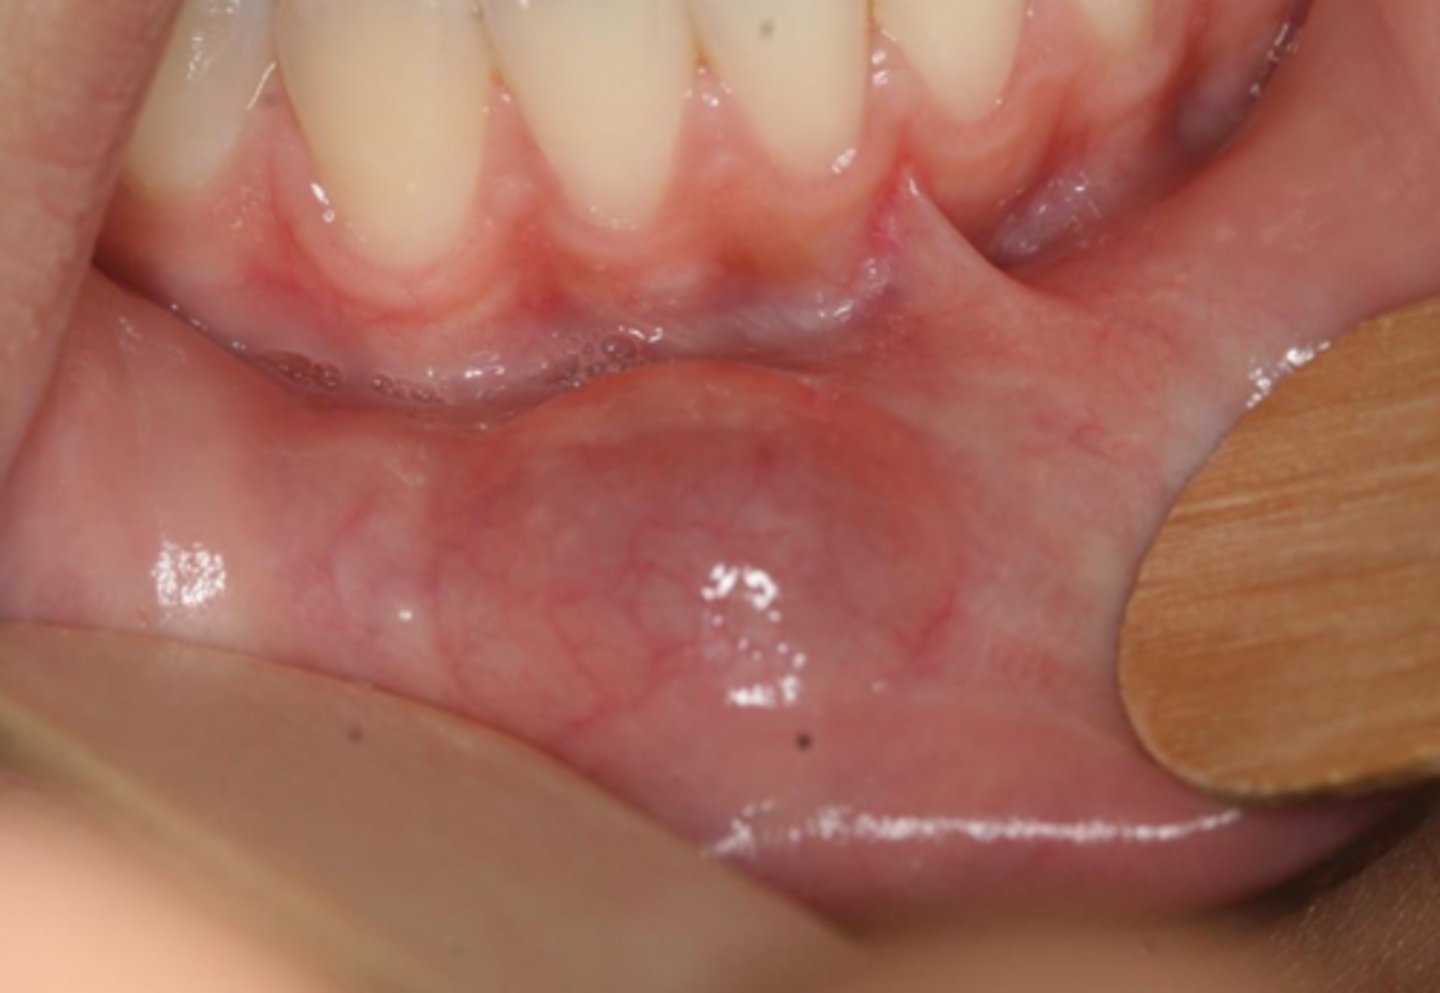

what reactive salivary gland lesion appears as a dome-shaped swelling with a bluish-translucent hue?

mucocele

what reactive salivary gland lesion is often due to trauma (pinching/biting/hitting) seen in children and young adults, mainly found in the lower lip, and occurs in those with a history of recurrent swelling that may periodically rupture?